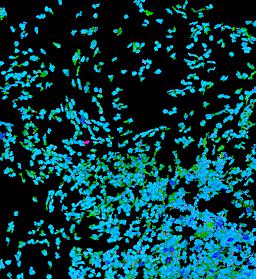

Pancreatic ductal adenocarcinoma is a lethal disease with limited treatment options and poor survival. We studied 83 spatial samples from 31 patients (11 treatment-naïve and 20 treated) using single-cell/nucleus RNA sequencing, bulk-proteogenomics, spatial transcriptomics and cellular imaging. Subpopulations of tumor cells exhibited signatures of proliferation, KRAS signaling, cell stress and epithelial-to-mesenchymal transition. Mapping mutations and copy number events distinguished tumor populations from normal and transitional cells, including acinar-to-ductal metaplasia and pancreatic intraepithelial neoplasia. Pathology-assisted deconvolution of spatial transcriptomic data identified tumor and transitional subpopulations with distinct histological features. We showed coordinated expression of TIGIT in exhausted and regulatory T cells and Nectin in tumor cells. Chemo-resistant samples contain a threefold enrichment of inflammatory cancer-associated fibroblasts that upregulate metallothioneins. Our study reveals a deeper understanding of the intricate substructure of pancreatic ductal adenocarcinoma tumors that could help improve therapy for patients with this disease.